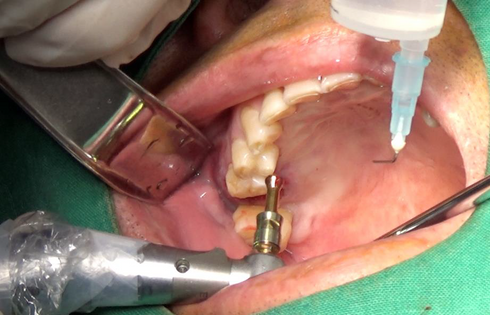

Safe sinus augmentation was performed using VAROGuide and VAROGuide Sinus Kit.

Bone graft was done and Healing abutment was connected.